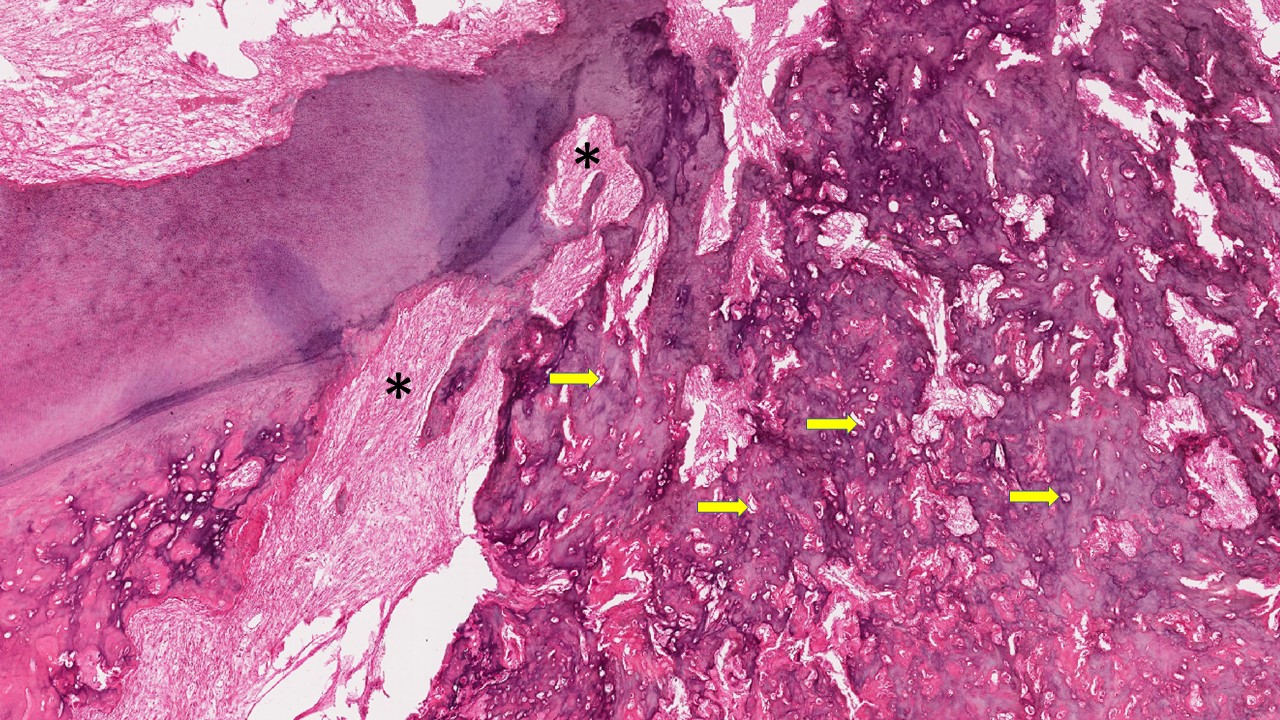

Descrição microscópica:

microscopicamente, o tumor é composto de um tecido mesenquimal rico em células, que lembra a papila dentária primitiva, misturado ao epitélio odontogênico em proliferação. O epitélio odontogênico pode apresentar um padrão de cordões longos e delgados, com frequência anastomosados e/ou um padrão de ilhas de epitélio odontogênico. Em ambos os padrões as células periféricas são colunares altas lembrando pré-ameloblastos e o centro das ilhas apresenta padrão de células epiteliais frouxamente dispostas lembrando o retículo estrelado.

Dados importantes para diagnóstico:

- Cordões de células epiteliais odontogênicas (setas pretas);

- Ilhas de células epiteliais odontogênicas (setas brancas);

- Células periféricas colunares altas empaliçadas (setas amarelas);

- Centro das ilhas lembrando retículo estrelado (asterisco);

- Tecido conjuntivo rico em células com núcleo volumoso e poucas fibras colágenas (estrela).